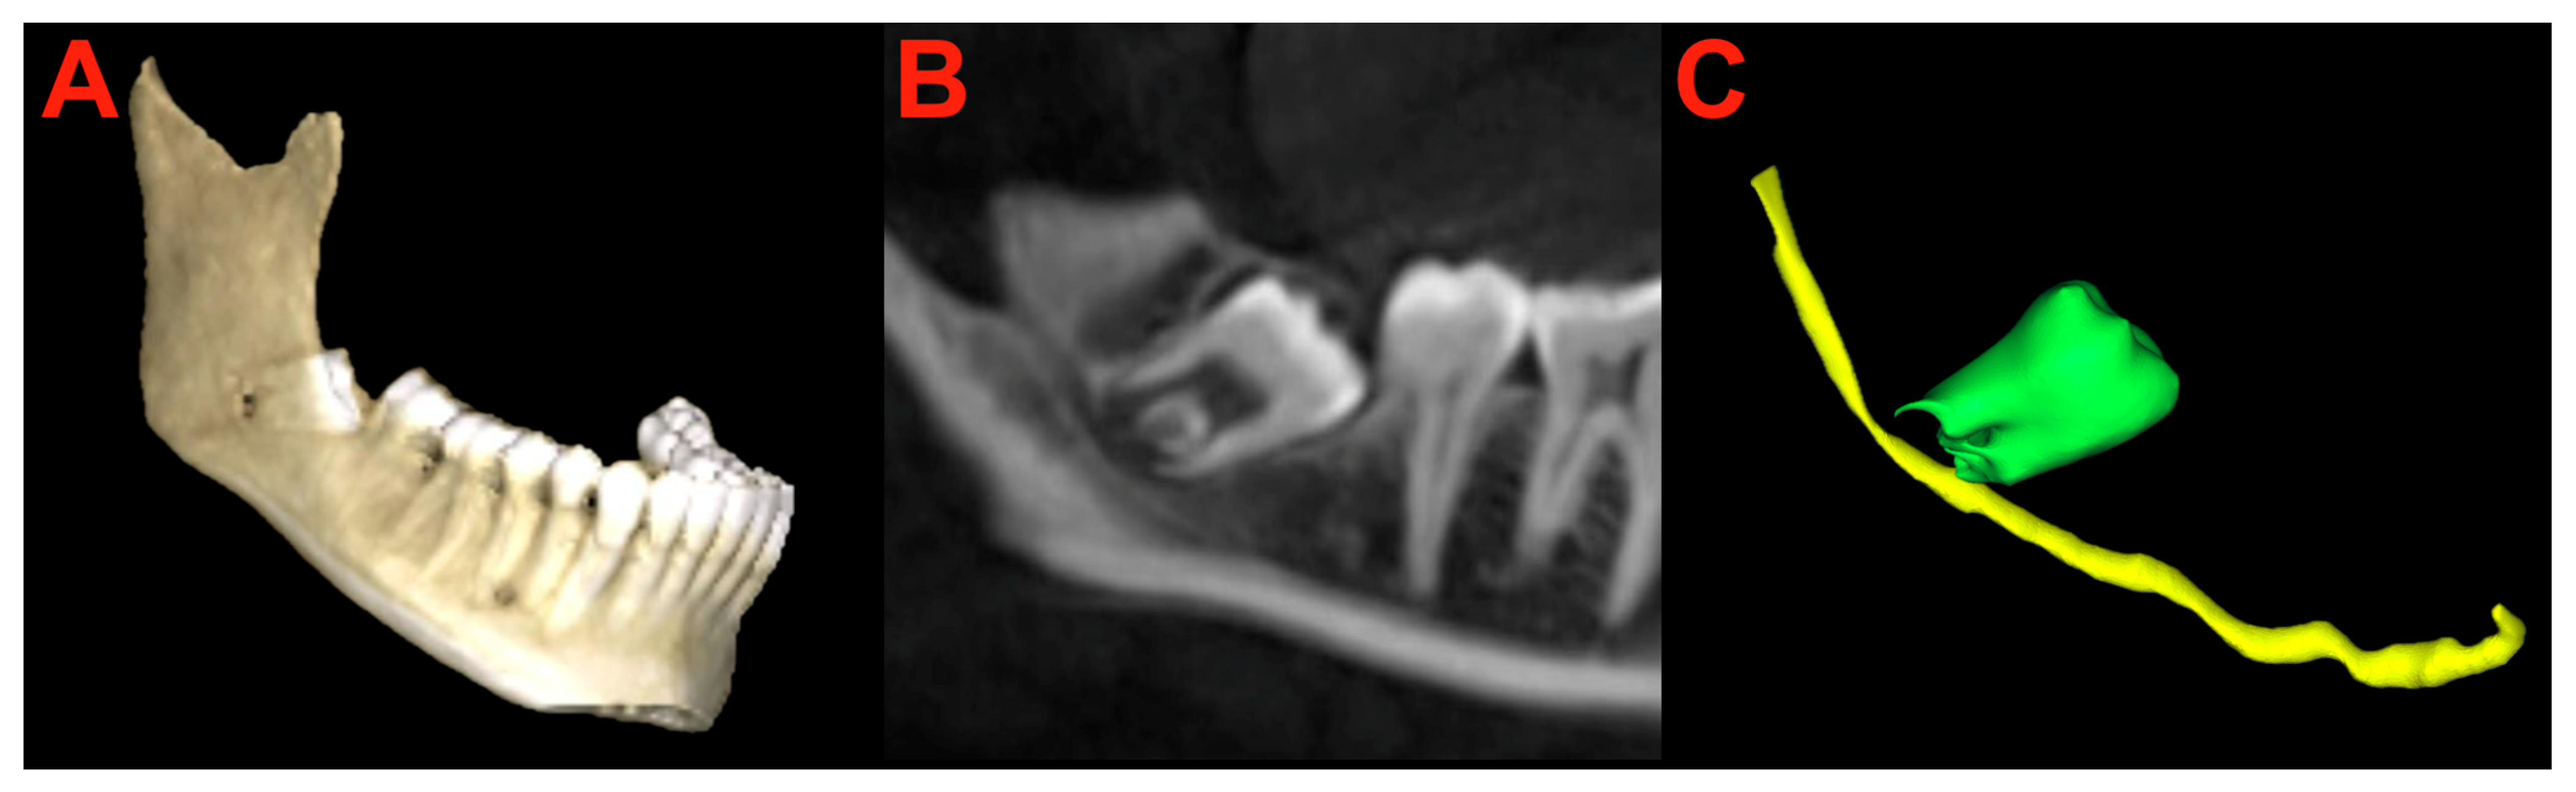

2.6. Segmentation and Preparation

2.7. Surgery